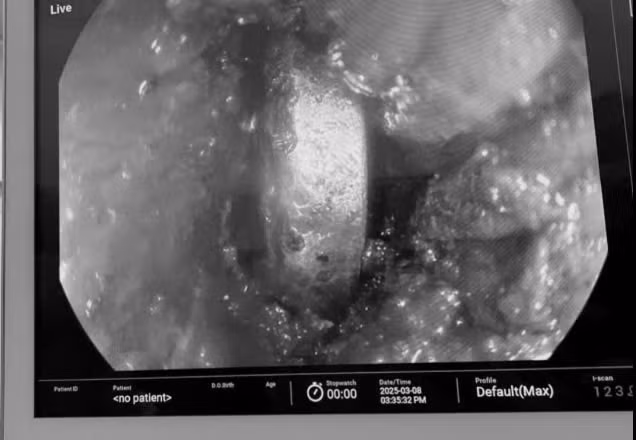

| Nội soi phát hiện dị vật pin cúc áo trong thực quản bệnh nhi. Ảnh BVCC |

Khi tiến hành nội soi, các bác sĩ xác định thực quản chu vi xung quanh pin đã loét hết, phía trên và phía dưới dị vật đều phù nề chít hẹp hết đường ra cũng như đường xuống dạ dày.